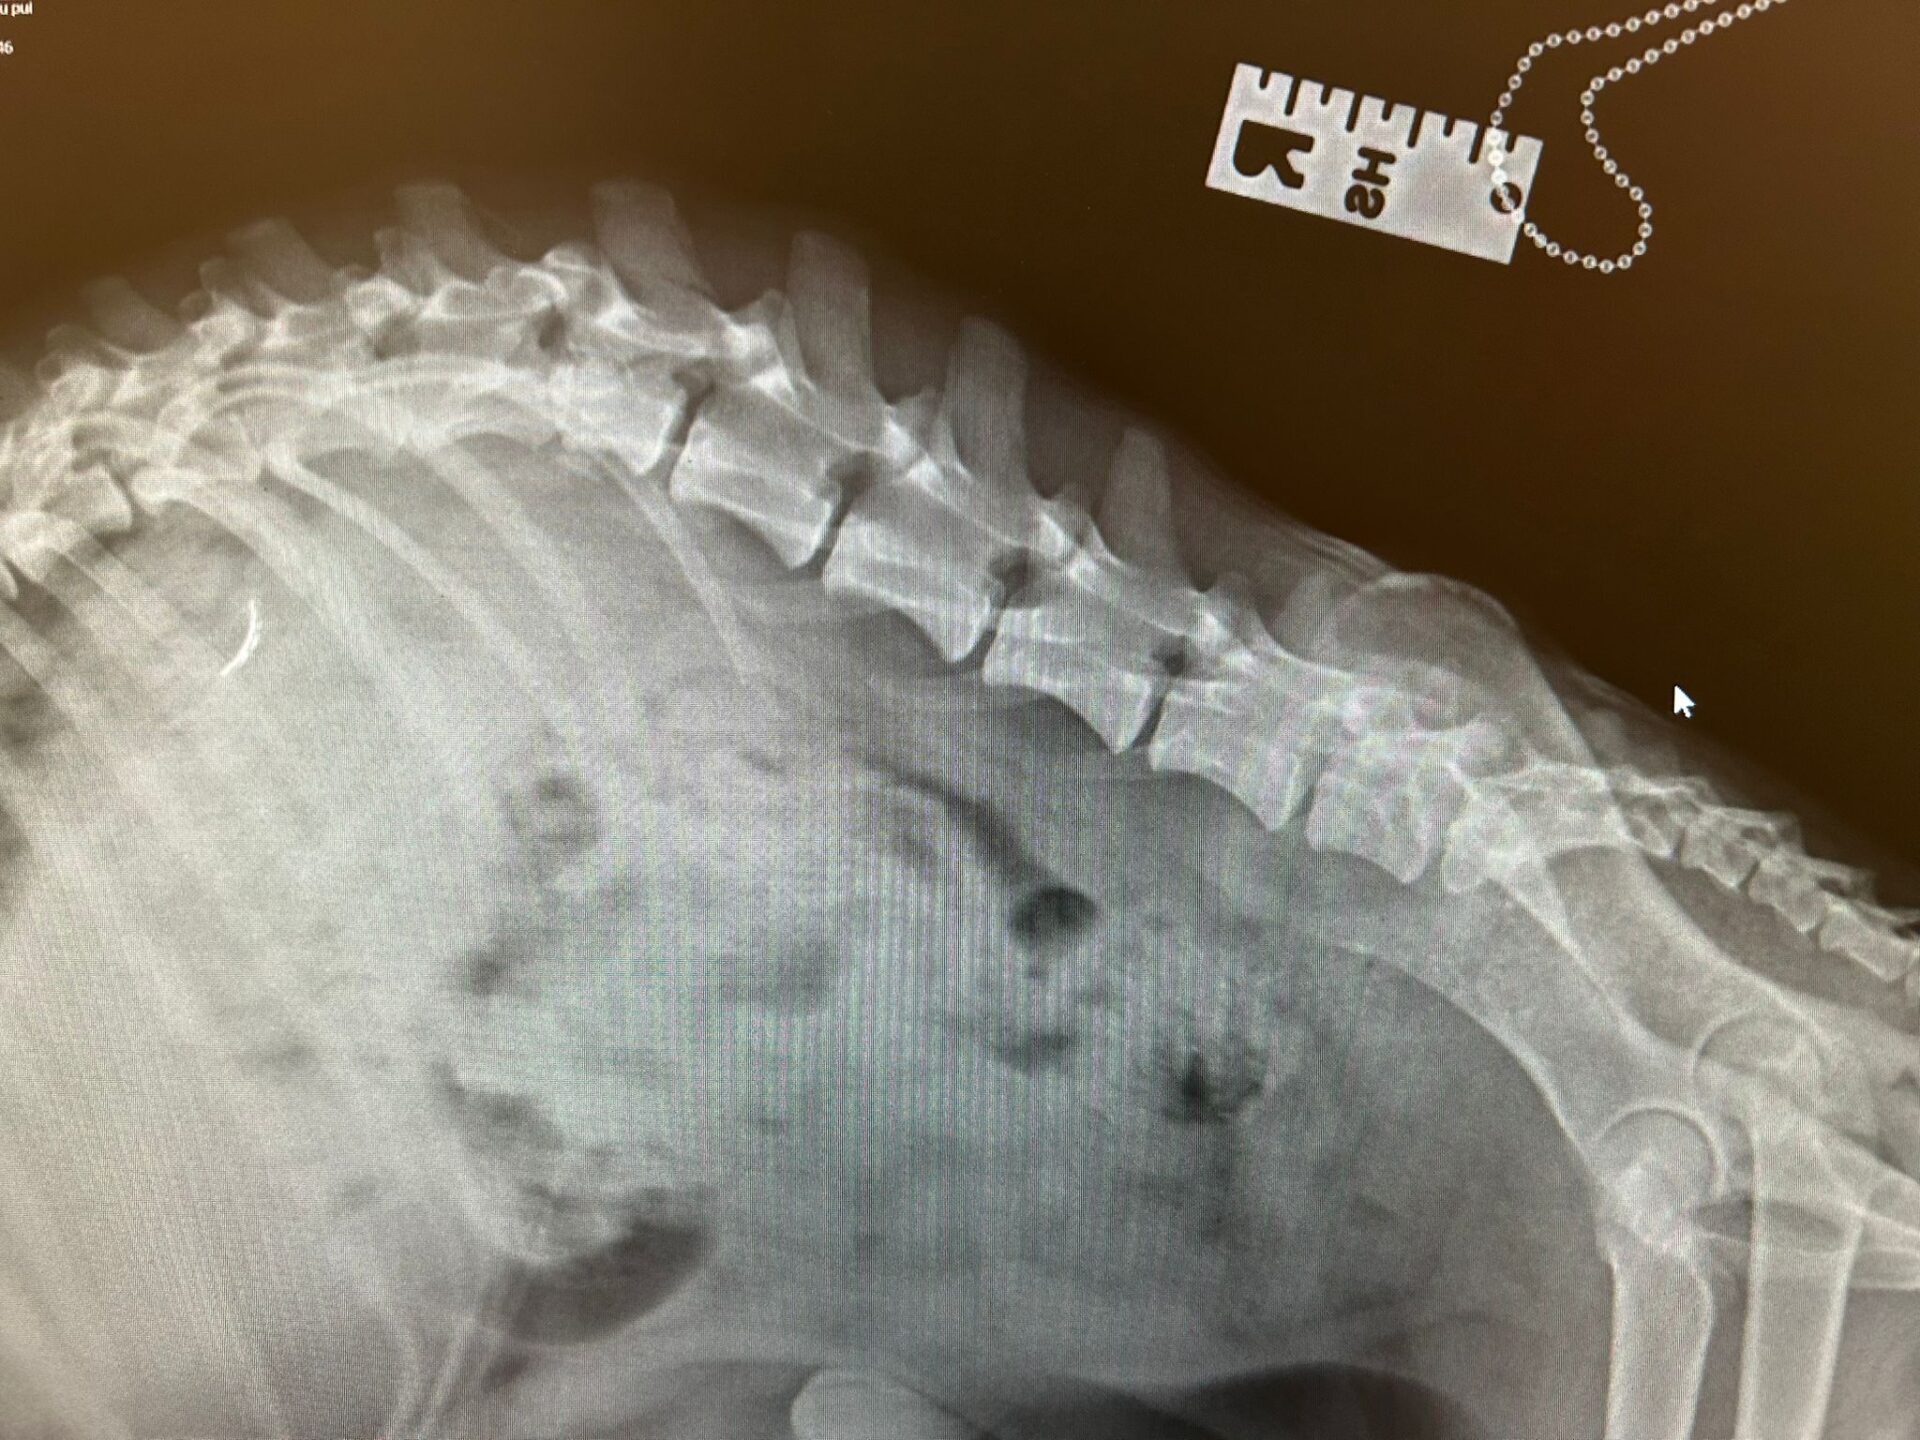

Pia konnte ihre Hinterbeine nicht bewegen und hatte eine alte Verletzung an der Wirbelsäule. Halb gelähmt muss sie ihre Welpen auf die Welt gebracht haben und niemand hat Pia geholfen.

Wir haben alle Hebel in Bewegung gesetzt, um Pia eine Operation von Fachärzten in Rumänien zu ermöglichen, welche sie gut überstanden hat. Gerne möchten wir uns an dieser Stelle noch einmal bei allen Spendern bedanken, die Pia bei ihren Tierarztschulden geholfen haben.